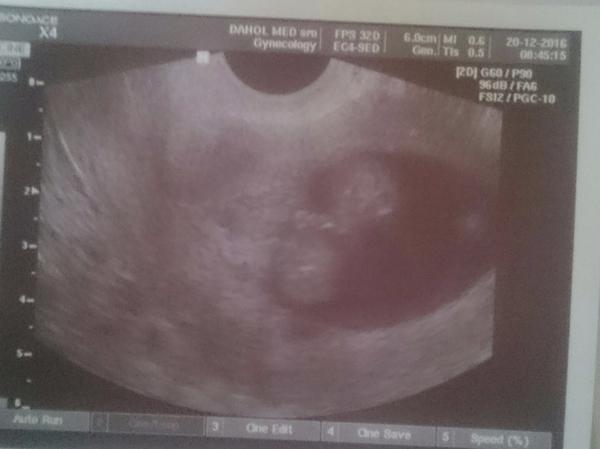

Ahojte baby ja som bola vcera u gynekologicky na rocnej kontrole. Robila mi sono a bol tam 19mm folikul vcera bol 21DC! Podla BT som mala ovulaciu 14-15DC vtedy klesla na 36,5 a potom stupla. BT bola dnes 37,1. Ja tomu nechapem mozeme sa este snazit? Moze byt este teraz ovulacia?

@kakatulik ved to som si myslela aj ja. Vcera ma s tym folikulom zaskocila. Este mi ho aj ukazala lebo som jej hovorila ze ovulka uz bola. Tak ja neviem.....